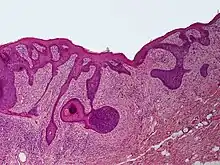

Perifollicular fibroma is a cutaneous condition, a benign tumor usually skin colored, most often affecting the face and upper trunk.[1]:674[2]